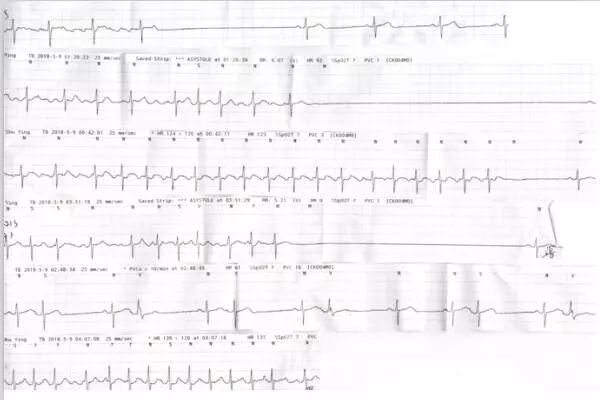

心电遥测:阵发性房颤,阵发性房扑,窦性停搏,R-R间期最长7.45秒(图2)。

图2. 心电遥测。